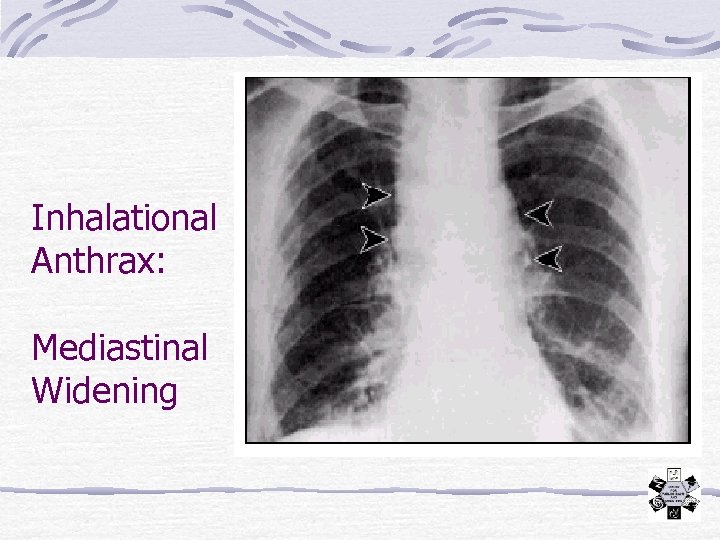

Inhalational Anthrax Incubation: 1 - 6 days (rarely up to > 60 days) Prodrome: 1 -2 d fever, malaise, dry cough Severe respiratory distress, septic shock, may have meningitis Diagnosis Hemorrhagic mediastinitis – wide on CXR Isolation Standard; not contagious

Inhalational Anthrax: Mediastinal Widening